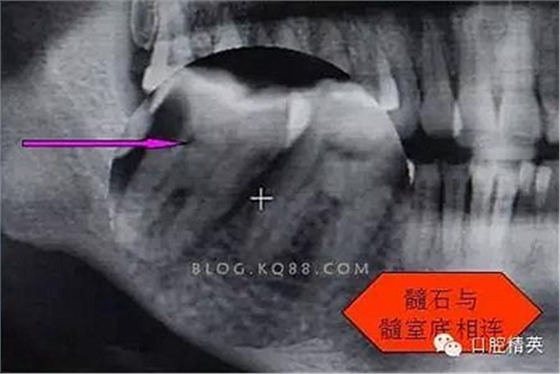

圖二

開髓后,發(fā)現(xiàn)是C型根管。

剛開始懷疑有增生的牙體組織,其實就是髓石。

3.開髓去腐后,髓腔基本就是這樣,在頰側(cè)近遠中都有根管口顯示,初步用8號C+銼去試探性探查根管,沒有阻力感,以為就是c型根管,舌側(cè)用C+銼時有阻力感覺,接上測量儀去探查根管,以防C+銼探通后超出根尖孔,最后舌根長度16mm*15號K銼(16.5mm*8號C+銼),機擴F2。接下來著重頰側(cè)的根管尋找,后來在頰側(cè)近遠中插入K銼時總覺得K銼尖段都指向一個位置,感覺不對,再次讀X線片,后來發(fā)現(xiàn)術(shù)前沒有仔細查看X線片,以及未回顧這位患者年齡,也就忘記牙齒的增齡性改變的含義。髓腔之所以小或者不清楚,一個因為年齡增加的原因二是因為牙齒長期受到外界物理化學刺激所導致髓腔變小,甚至沒有髓腔顯影。本病例患者,髓腔有大概顯影,但髓室里好像有增生的牙體組織,其實就是髓石。并且和髓室底相連接。如果不注意,有可能按常規(guī)預備方法進行預備。